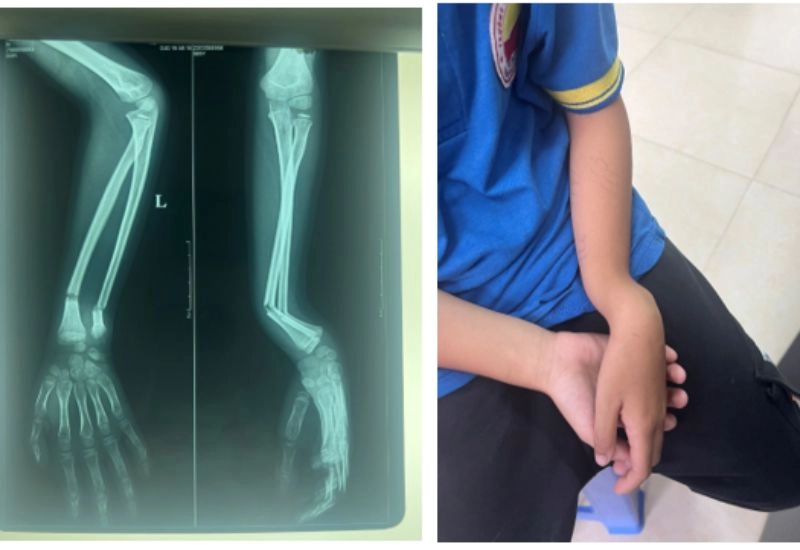

Tại vị trí xương bị gãy có thể bị biến dạng như cong, lệch, thay đổi hình dạng so với bình thường.dấu hiệu nhận biết gãy xương

Dấu hiệu gãy xương cẳng tay (gãy xương kín) ảnh minh họa.